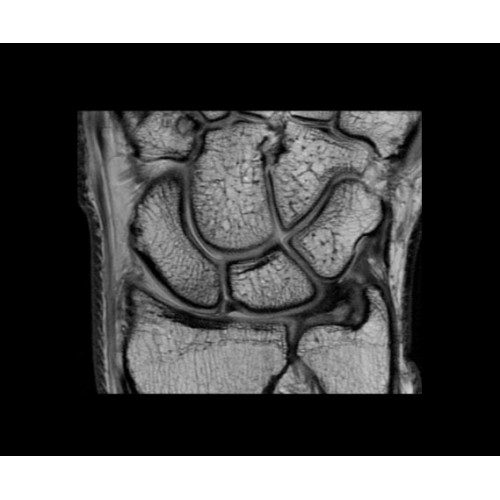

Поле обзора 50x50x50 см и апертура шириной 70 см позволят достоверно визуализировать сложные анатомические области для пациентов с крупным телосложением, например, плечи и бедра. Феноменальная однородность системы SIGNA Architect обеспечивает наиболее широкое поле обзора с улучшенными характеристиками градиентов. Ничто не останется незамеченным.

• OrthoWorks — программное решение для визуализации структур опорно-двигательного аппарата с прекрасным контрастированием тканей.